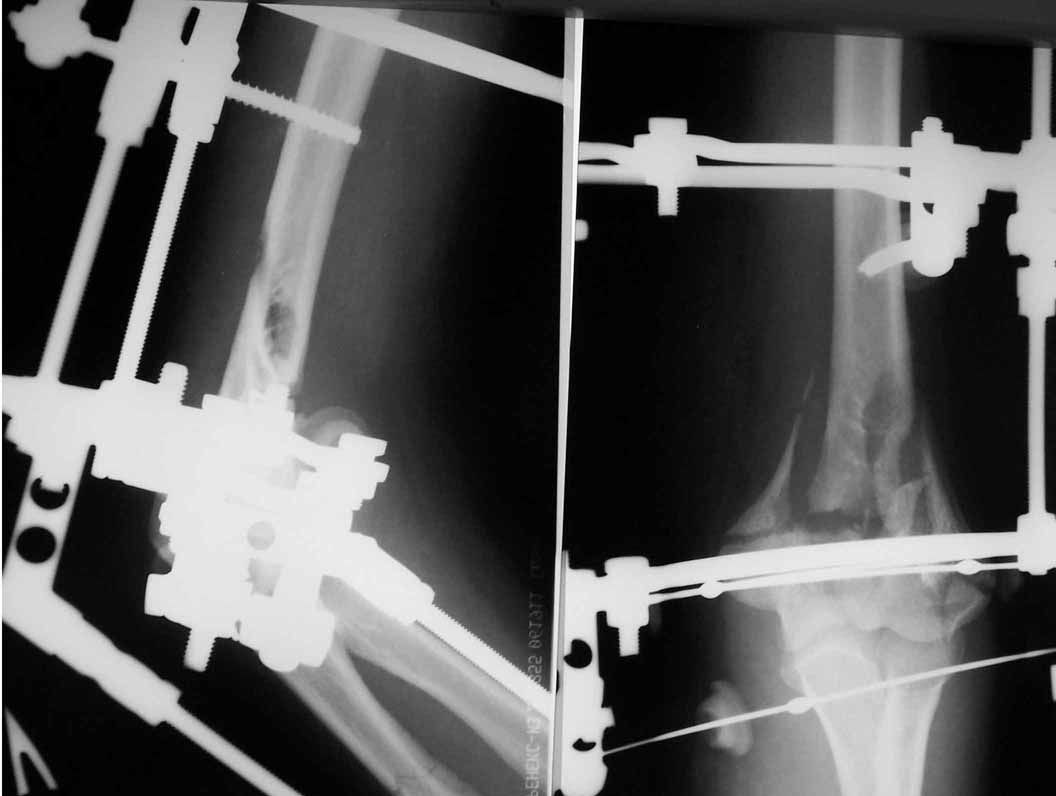

Alexander Artemiev 14 Сентябрь 2005, 16:19

Женщина 42 лет, операция через неделю после перелома.

Д-з - открытый перелом мыщелков со смещзением и локтевой кости

без смещения - падение с лошади.

До операции снимки не очень, тем более в гипсе.

Остеосинтез закрытый (если так можно выразиться), т.е. без

разрезов. Длительность операции - около 1,5 часа со студентом.

6 щелчков ЭОПом.